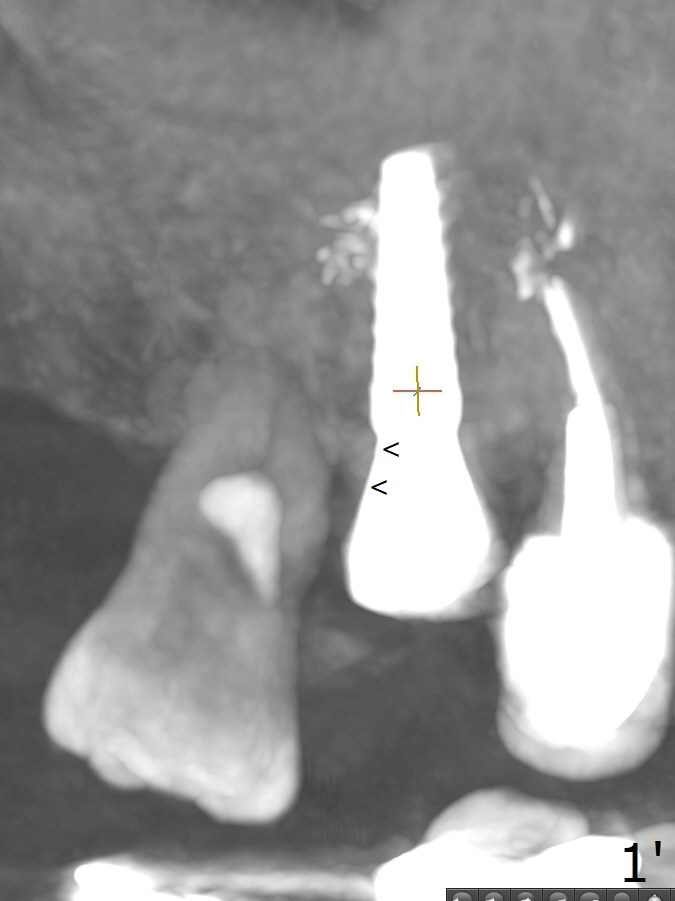

A 5.5 mm profile drill is used for the distal crest (Fig.1' arrowheads) prior to placement of 6x4 mm healing abutment.